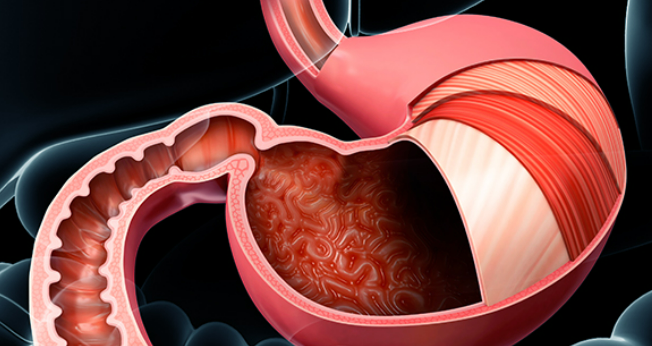

위내시경 검사는 위나 십이지장, 식도를 내시경 카메라로 살펴보는 검사로 평소 소화가 잘 되지 않거나 더부륵함, 메스꺼움, 복통, 속 쓰림, 구토 증상 등이 있다면 위염, 역류성식도염, 위용종, 위궤양, 위출혈, 십이지장질환, 위암, 식도암 등이 있을 수 있으므로 꼭 해보는 것을 권장드립니다.